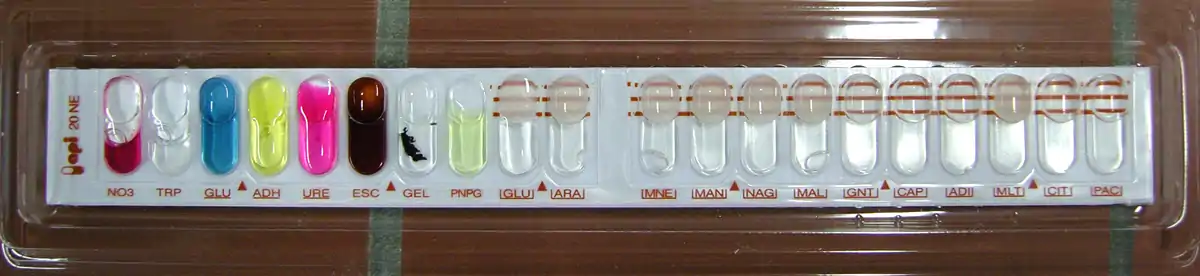

Analytical profile index

An analytical profile index is a fast identification system based on biochemical incubation tests. Usually, this test is used to quickly diagnose clinically relevant bacteria by allowing physicians to run about 20 tests at one time.[19]